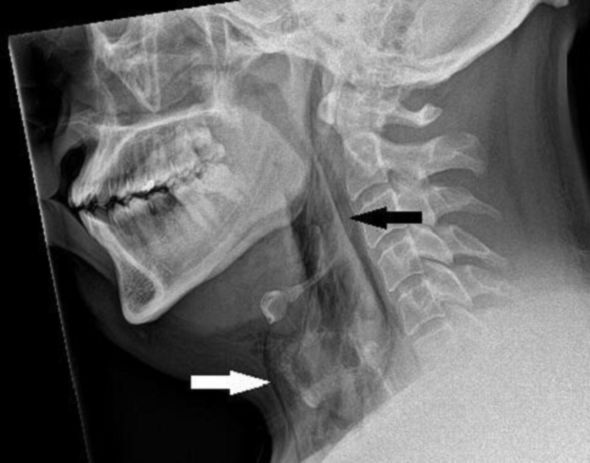

Boynun rentgenoqrafiyasından məlum olub ki, kişidə cərrahi amfizem var. Bu vəziyyətdə hava dərinin altındakı toxumanın ən dərin təbəqələri altına yığılır. Daha sonra kompüter tomoqrafiyası (KT) skaneri göstərib ki, yırtıq onun boynunun üçüncü və dördüncü fəqərələri arasındadır. Sinəsinin ağciyərləri arasındakı boşluqda da hava toplanıb.